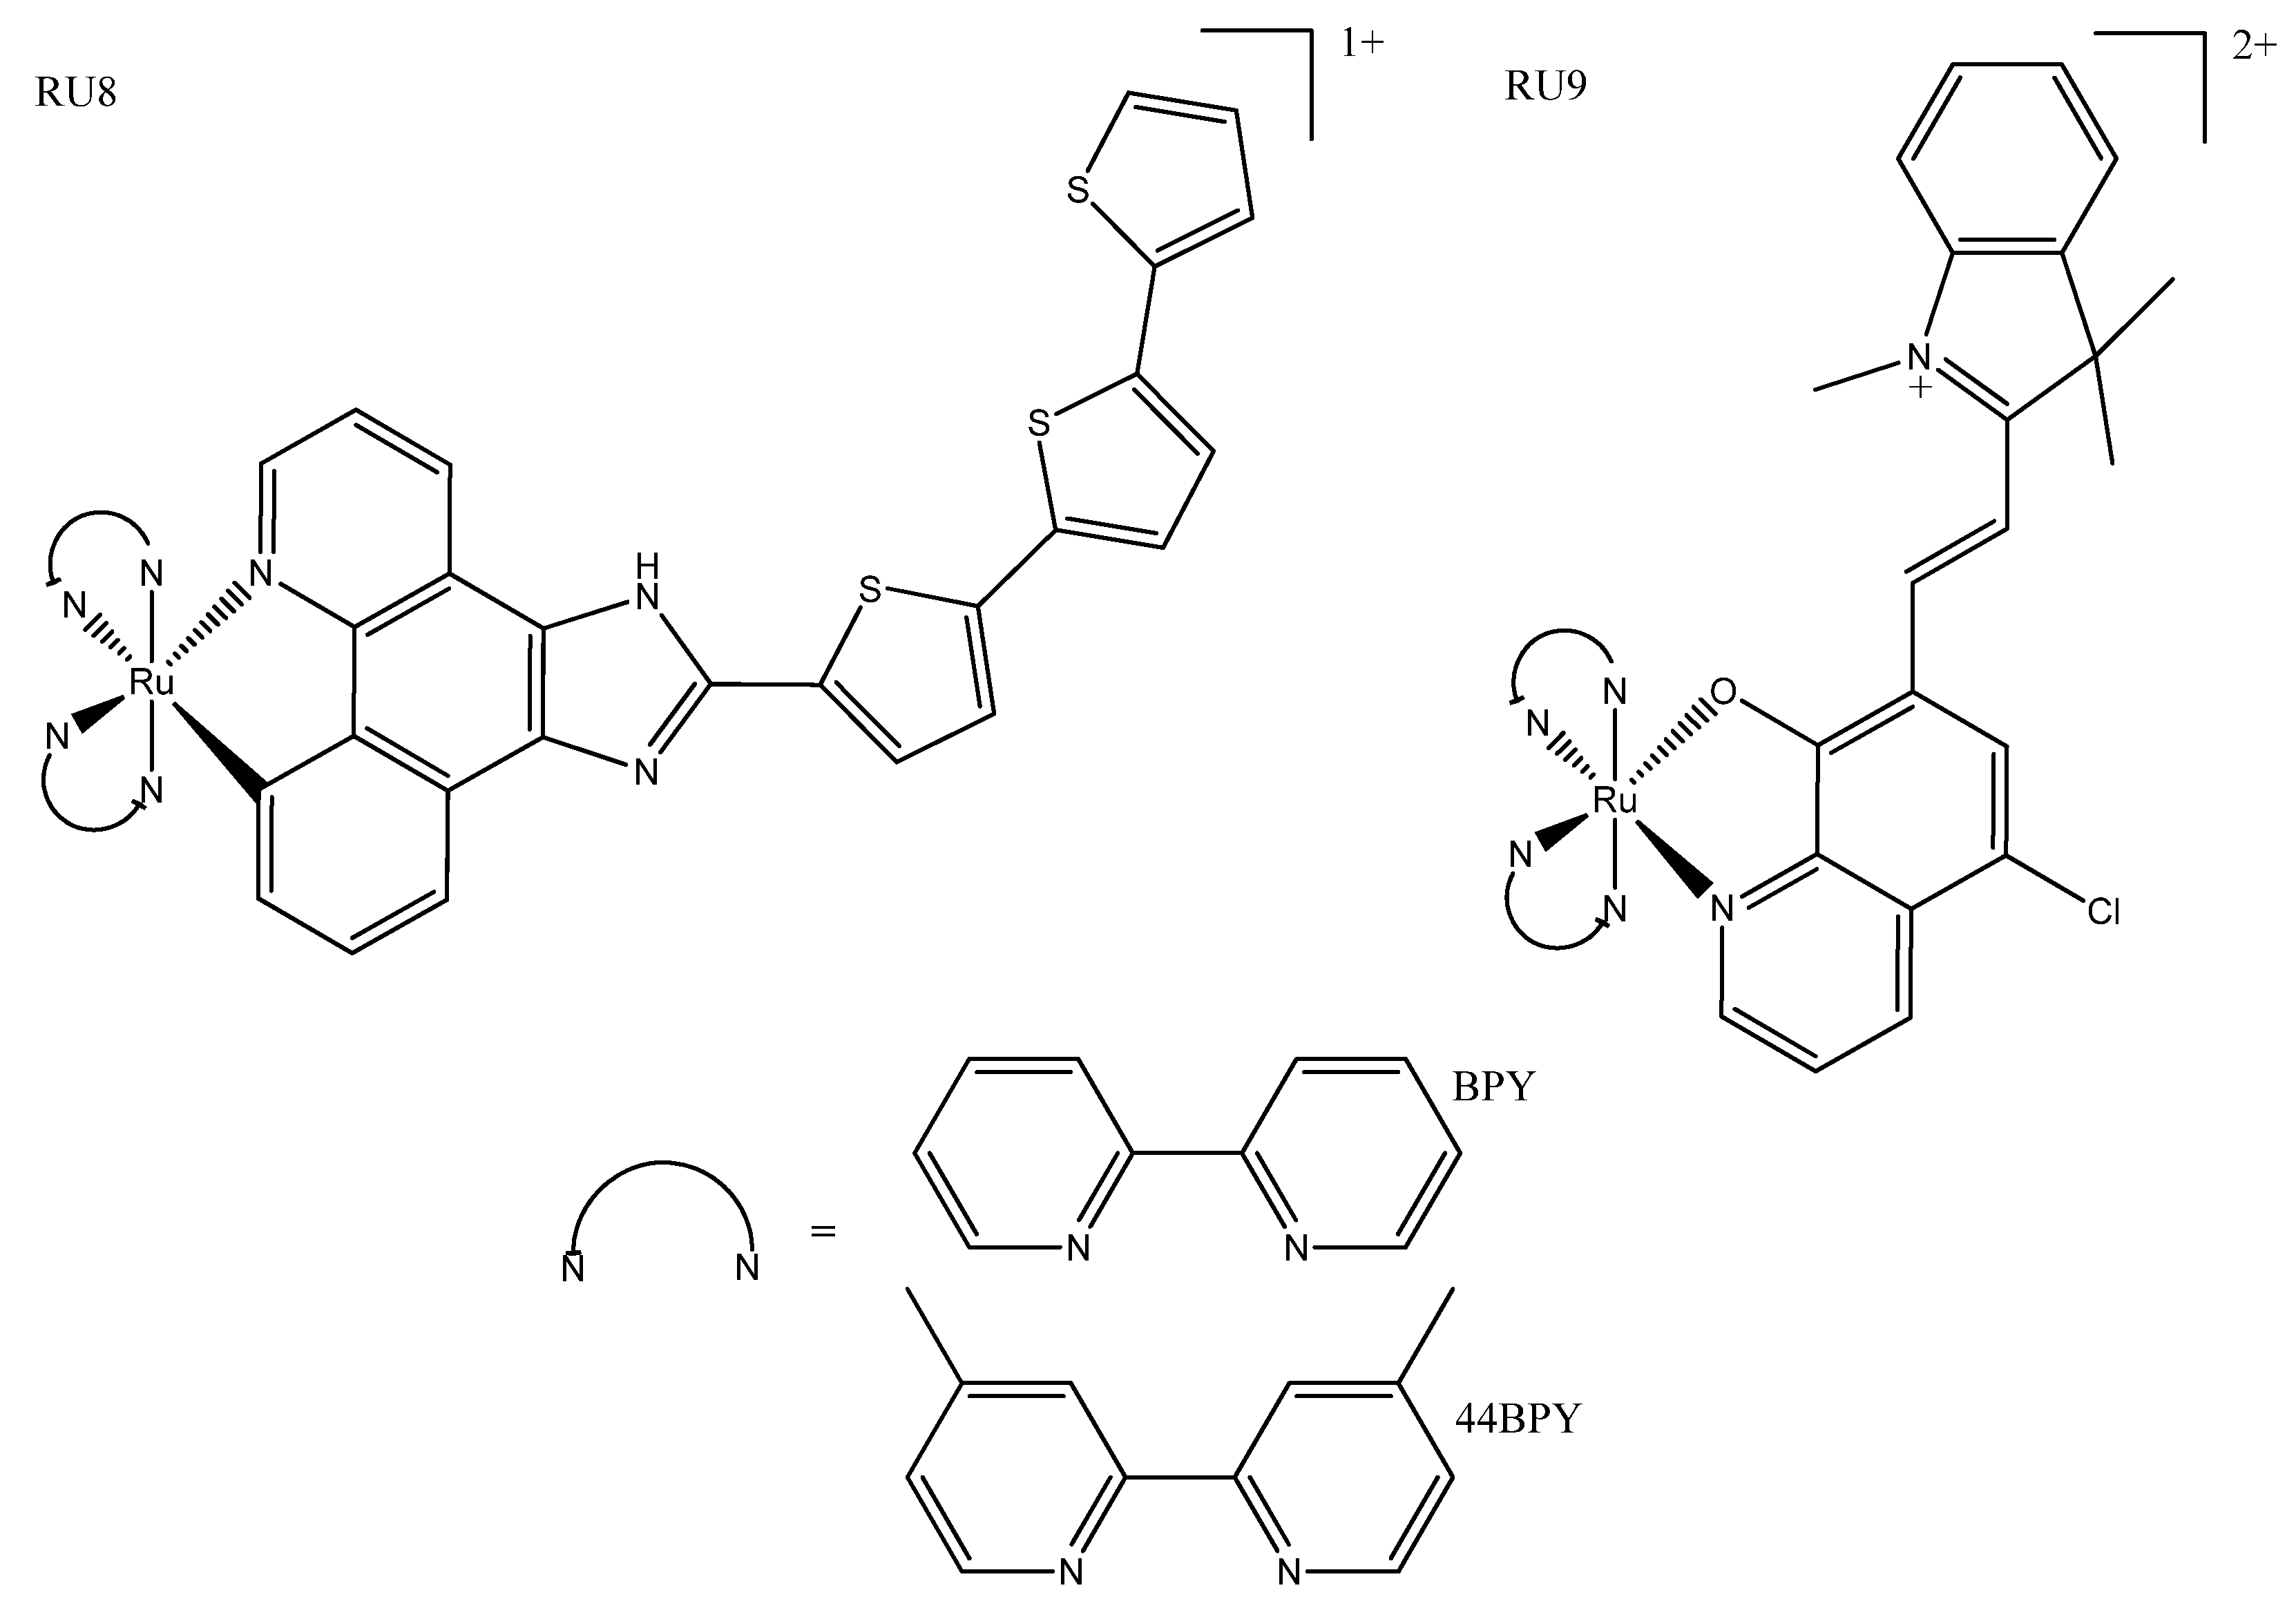

3. Ruthenium Complexes

3.2. Piano Stool Complexes

3.3. Cyclometallated/Diverse Coordination Sphere

3.4. Other

- Ghosh, G.; Colón, K.L.; Fuller, A.; Sainuddin, T.; Bradner, E.; McCain, J.; Monro, S.M.A.; Yin, H.; Hetu, M.W.; Cameron, C.G.; et al. Cyclometalated Ruthenium(II) Complexes Derived from α-Oligothiophenes as Highly Selective Cytotoxic or Photocytotoxic Agents. Inorg. Chem. 2018, 57, 7694–7712. [Google Scholar] [CrossRef]

- McCain, J.; Colón, K.L.; Barrett, P.C.; Monro, S.M.A.; Sainuddin, T.; Roque Iii, J.; Pinto, M.; Yin, H.; Cameron, C.G.; McFarland, S.A. Photophysical Properties and Photobiological Activities of Ruthenium(II) Complexes Bearing π-Expansive Cyclometalating Ligands with Thienyl Groups. Inorg. Chem. 2019, 58, 10778–10790. [Google Scholar] [CrossRef]

- Zhang, Y.; Zhou, Q.; Tian, N.; Li, C.; Wang, X. Ru(II)-Complex-Based DNA Photocleaver Having Intense Absorption in the Phototherapeutic Window. Inorg. Chem. 2017, 56, 1865–1873. [Google Scholar] [CrossRef]

- Saeed, H.K.; Jarman, P.J.; Archer, S.; Sreedharan, S.; Saeed, I.Q.; Mckenzie, L.K.; Weinstein, J.A.; Buurma, N.J.; Smythe, C.G.W.; Thomas, J.A. Homo- and Heteroleptic Phototoxic Dinuclear Metallo-Intercalators Based on RuII(dppn) Intercalating Moieties: Synthesis, Optical, and Biological Studies. Angew. Chem. 2017, 56, 12628–12633. [Google Scholar] [CrossRef]

- Zhao, Z.; Hu, R.; Shi, H.; Wang, Y.; Ji, L.; Zhang, P.; Zhang, Q. Design of Ruthenium-Albumin Hydrogel for Cancer Therapeutics and Luminescent Imaging. J. Inorg. Biochem. 2019, 194, 19–25. [Google Scholar] [CrossRef]

- Mascheroni, L.; Dozzi, M.V.; Ranucci, E.; Ferruti, P.; Francia, V.; Salvati, A.; Maggioni, D. Tuning Polyamidoamine Design to Increase Uptake and Efficacy of Ruthenium Complexes for Photodynamic Therapy. Inorg. Chem. 2019, 58, 14586–14599. [Google Scholar] [CrossRef]

- Yang, J.; He, X.; Ke, Z.; Chen, J.; Zou, Z.; Wei, B.; Zou, D.; Zou, J. Two Photoactive Ru (II) Compounds Based on Tetrazole Ligands for Photodynamic Therapy. J. Inorg. Biochem. 2020, 210, 111127. [Google Scholar] [CrossRef]

- Nehru, S.; Veeralakshmi, S.; Kalaiselvam, S.; Subin David, S.P.; Sandhya, J.; Arunachalam, S. DNA Binding, Antibacterial, Hemolytic and Anticancer Studies of Some Fluorescent Emissive Surfactant-Ruthenium(II) Complexes. J. Biomol. Struct. Dyn. 2021, 39, 2242–2256. [Google Scholar] [CrossRef]

- Zhao, Z.; Zhang, X.; Li, C.-E.; Chen, T. Designing Luminescent Ruthenium Prodrug for Precise Cancer Therapy and Rapid Clinical Diagnosis. Biomaterials 2019, 192, 579–589. [Google Scholar] [CrossRef]

- Li, H.; Xie, C.; Lan, R.; Zha, S.; Chan, C.-F.; Wong, W.-Y.; Ho, K.-L.; Chan, B.D.; Luo, Y.; Zhang, J.-X.; et al. A Smart Europium-Ruthenium Complex as Anticancer Prodrug: Controllable Drug Release and Real-Time Monitoring under Different Light Excitations. J. Med. Chem. 2017, 60, 8923–8932. [Google Scholar] [CrossRef]

- Dos Santos, J.S.; Ramos, L.C.; Ferreira, L.P.; Campo, V.L.; de Rezende, L.C.D.; da Silva Emery, F.; Santana da Silva, R. Cytotoxicity, Cellular Uptake, and Subcellular Localization of a Nitrogen Oxide and Aminopropyl-β-Lactose Derivative Ruthenium Complex Used as Nitric Oxide Delivery Agent. Nitric Oxide Biol. Chem. 2019, 86, 38–47. [Google Scholar] [CrossRef]

- Weynand, J.; Diman, A.; Abraham, M.; Marcélis, L.; Jamet, H.; Decottignies, A.; Dejeu, J.; Defrancq, E.; Elias, B. Towards the Development of Photo-Reactive Ruthenium(II) Complexes Targeting Telomeric G-Quadruplex DNA. Chemistry 2018, 24, 19216–19227. [Google Scholar] [CrossRef]

| TDL1433 | 137 ± 3 | 1.9 ± 0.1 (400-700) | 525 | Optimized clinical procedure and completion of human clinical trials. | |||

| RU1 | 36.5 ± 3.0 | 3.1 ± 0.6 (420) | 620 | 420 | Photosensitizers for one- and two-photon PDT. | ||

| RU3 | 123 ± 3.62 | 3.77 ± 0.18 | 557/640 | 413 | Activated at multiple wavelengths; tracking possible both before and after photo treatment. | ||

| RU4a | 13 ± 2 | 0.47 ± 0.01 ** | 614 | 440 | Shows how modification of ancillary ligand and lipophilicity enhances therapeutic effect. | ||

| RU4b | 11 ± 3 | 2 ± 1 ** | 643 | 418 | |||

| RU6 | 83.1 ± 6.2 * | 34.1 ± 2.4 (460) | 500 | 355 | Slight variations in structure led to phototoxic or other photoactivated complexes. | ||

| RU6 | 31.3 ± 4.5 | 11.5 ± 2.5 (488) | 534 | 440 | Tagged with napthalamide derivative to target DNA. | ||

| RU8a | >300 | 12.0 ± 0.4 (633) | 805 | 540 | More lipophilic and absorption; more red-shifted than their non-cyclometallated counterparts. | ||

| RU8b | >300 | 16.6 ± 1.53 (625) | 728 | 550 | |||

| RU16 | 277.0 ± 7.1 | 32.5 ± 8.2 (488) | 570-750 | 350 | The linker could be irradiated at different wavelengths for different functionalization (prodrug activation or fluorescence). | ||